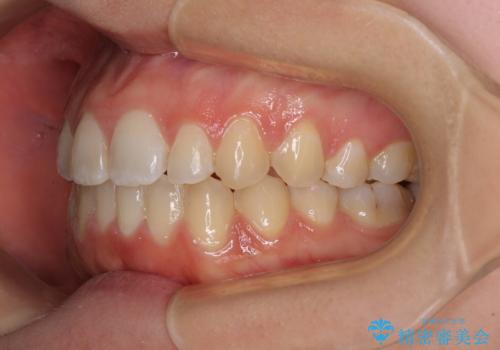

- 前歯の上下スペースによる食べにくさを気にして来院された患者様です。

インビザラインにより上下の前歯の隙間を閉じていくこととしました。

前歯のデコボコの解消と並行して上下の奥歯を圧下させるようにすることで、前歯を接触させるように計画しました。

上下の隙間に舌が入り込むことがオープンバイトの原因であったため、舌の筋肉のトレーニングも並行して行い、後戻りの抑制を図りました。